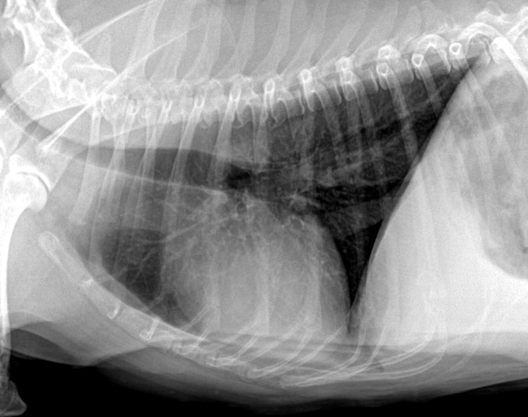

| Thorax | |

| Airways |

| ์ ์์ ์ธ ๊ณต๊ธฐ์ ํ๋ฆ : Trachea - Bronchus - Bronchioles - Lung |